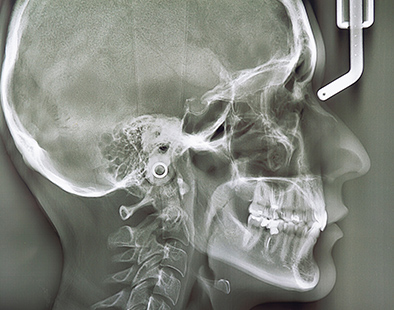

精度の高い診断があってこそ、安全性が高く、効果が期待できる治療の提供が可能となります。当院では、歯科用CT、頭部専用のセファログラム、デジタルレントゲン、口腔内スキャナーなど、先進的な設備機器が充実しており、精密な検査、高精度の診断に役立てています。

セファログラム